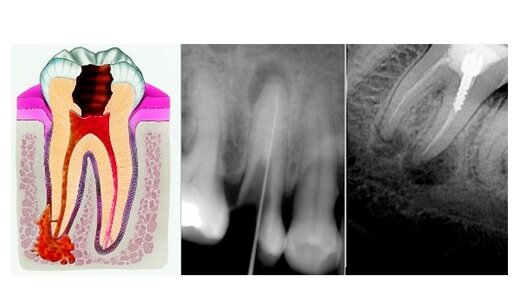

Апикальный периодонтит: причины патологии

Апикальный периодонтит представляет из себя патологию ткани зуба, при которой происходит разрушение периодонтальной связки, обсеменение микробной флорой системы корневых каналов, разрушение прилежащей кости в области верхушки зуба. Протекает в острой и хронической формах, каждой из которых соответствуют свои симптомы и , соответственно, требуется определенное лечение. Причины Способствовать заболеванию могут как экзо- так и эндогенные причины. Быстрота развития периодонтита зависит от длительности действия патогенного фактора, иммунитета, особенностей строения зубов и костной ткани челюстей...